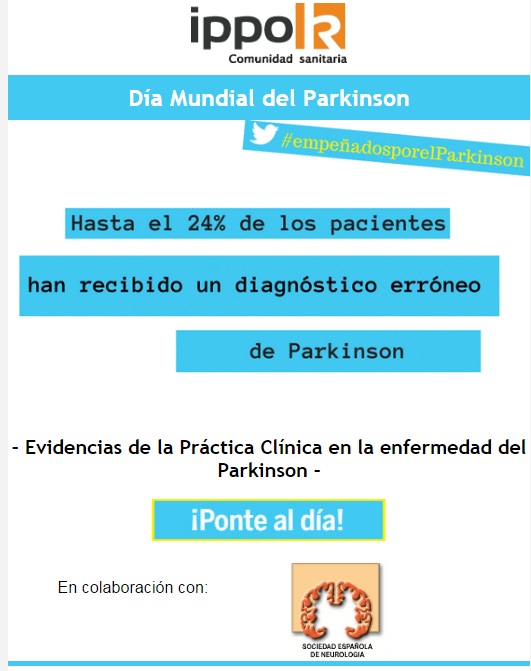

Con motivo de la conmemoración, el 11 de abril, del Día Mundial del Parkinson, la Sociedad Española de Neurología ha colaborado con Ippok Comunidad Sanitaria (la Comunidad de Diario Médico y Correo Farmacéutico) en la elaboración de un Quiz Interactivo sobre esta enfermedad.

Con motivo de la conmemoración, el 11 de abril, del Día Mundial del Parkinson, la Sociedad Española de Neurología ha colaborado con Ippok Comunidad Sanitaria (la Comunidad de Diario Médico y Correo Farmacéutico) en la elaboración de un Quiz Interactivo sobre esta enfermedad.

Si es usuario de Ippok puede acceder al mismo en el siguiente enlace: http://www.ippok.com/quiz/evidencias-de-la-practica-clinica-en-la-enfermedad-del-parkinson-ponte-al-dia